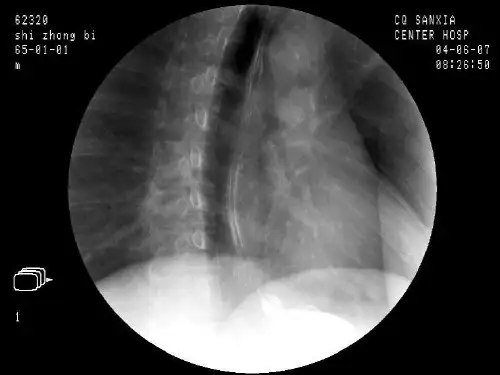

5分钟读懂消化道造影片(胃篇)

今天给大家推送一组胃部疾病的经典消化道造影表现。

一、正常胃粘膜

二、胃溃疡

三、胃恶性溃疡

四、胃部肿瘤

五、胃底憩室

六、胃息肉

七、胃息肉恶变

八、胃粘膜脱垂

九、胃扭转

十、幽门肥厚

十一、胃底平滑肌瘤

十二、胃大部切除(毕Ⅰ式)术后

十三、胃空肠吻合